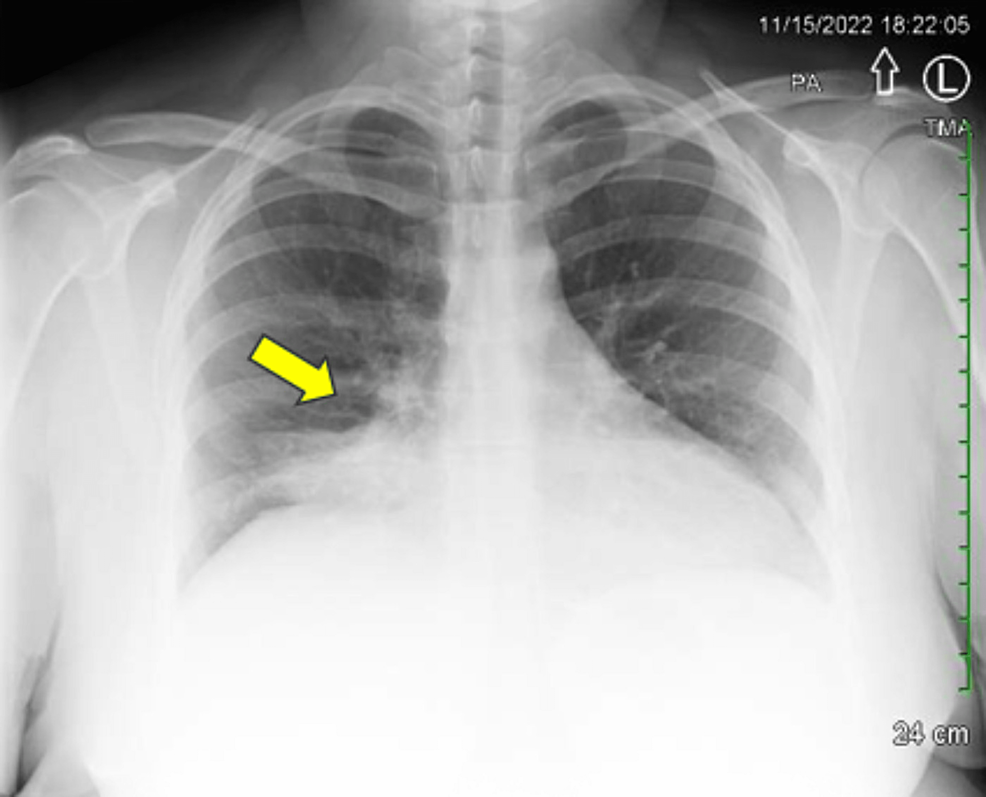

Masquerading as Pneumonia A Lung Neuroendocrine Tumor Case Report Cureus How Big Is A 3 Cm Lung Tumor Stage 3 — some tumors may be smaller than 3 centimeters across, while others are larger than 7 centimeters across. It has not reached the membranes that surround the lungs, and it does not affect the. Stage 3a, 3b, and 3c carcinoid lung tumors are even larger, or they have spread to multiple lymph nodes or other chest structures or. How Big Is A 3 Cm Lung Tumor.